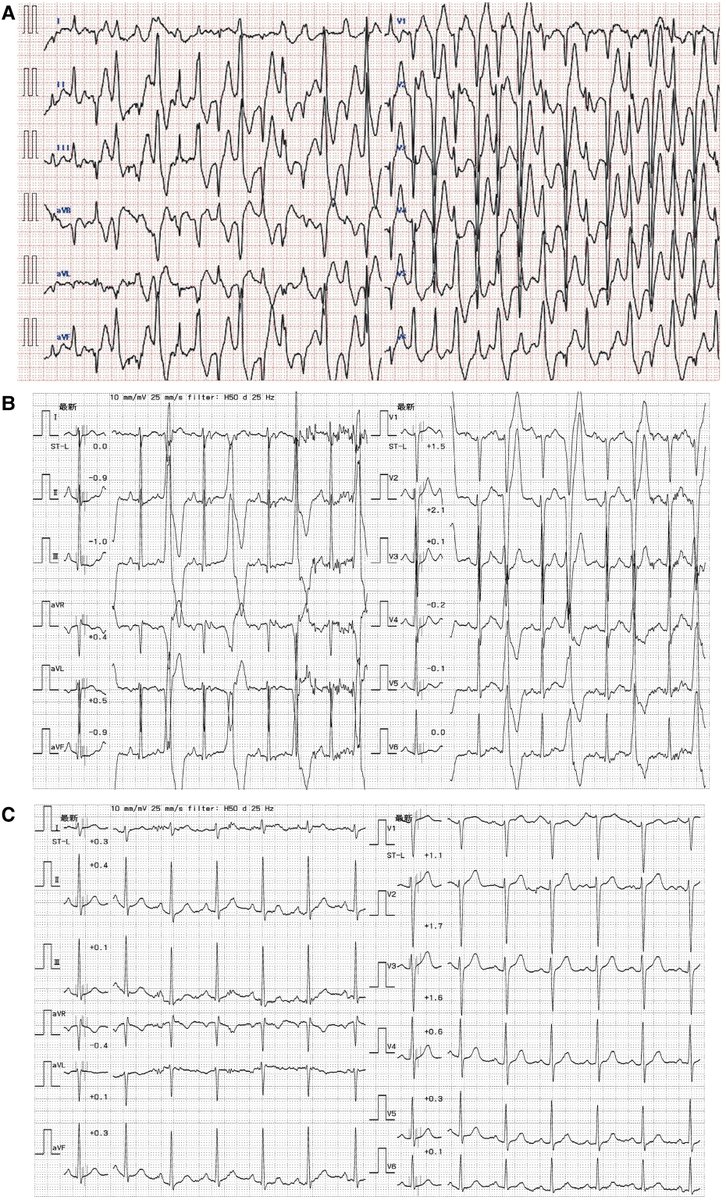

When Charcot-Marie-Tooth disease leads to electrical storm ow.ly/HeBg50VOOT3 #EHJCaseReports Philipp Sommer Tee Joo YEO Aaysha Cader Boldizsar Kovacs Erik Rafflenbeul A.Nazmi Calik Obayda Azizy Sara Moscatelli EHJCaseReports Editor-in-Chief #CardioX #EPeeps